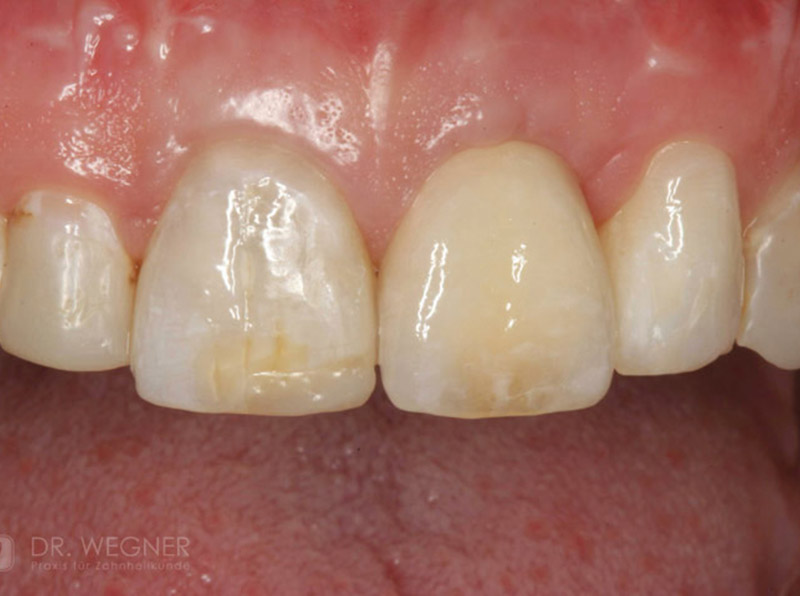

Unter dentalen Implantaten versteht man im allgemeinen eine Schraube, die dort, wo ein oder mehrere Zähne verloren gegangen sind, in den Kieferknochen "eingepflanzt" wird. Diese Therapieform der Implantologie hat sich in den letzten Jahren zu einem alltäglichen Therapieverfahren in der Zahnheilkunde entwickelt. Wissenschaftliche Untersuchungen zeigen hierfür eine Erfolgsquote von i. d. R. 80-98 % über 10 Jahre. Verglichen mit anderen zahnärztlichen Maßnahmen gibt es nahezu keine andere Therapie mit derart guten Erfolgsaussichten. Auch eine Verbesserung der Lebensqualität wird durch implantatgetragenen Zahnersatz laut klinischer Studien erreicht.

Mittlerweile hat sich die Implantologie zu einem alltäglichen Therapieverfahren mit sehr guten Erfolgsaussichten in der Zahnheilkunde entwickelt. Bei guter Mundhygiene und regelmäßigen Kontrolluntersuchungen können fachmännisch gesetzte Zahnimplantate ein Leben lang halten.